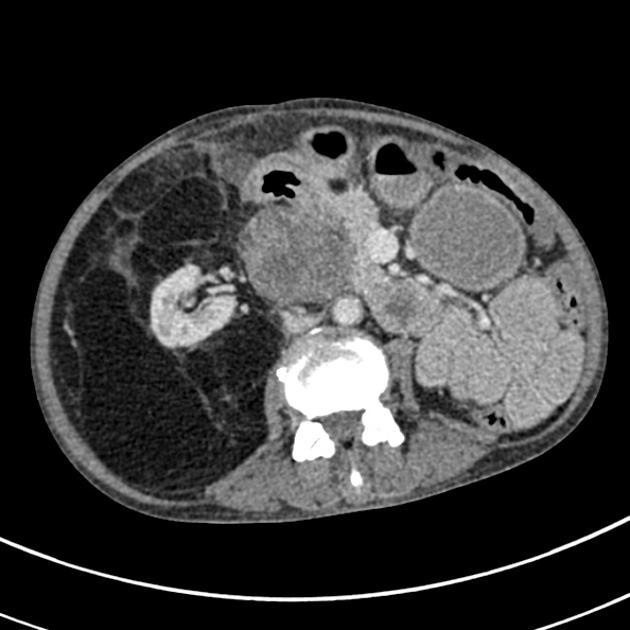

retroperitoneal liposarcoma

10–15% of all liposarcomas arise from the retroperitoneum